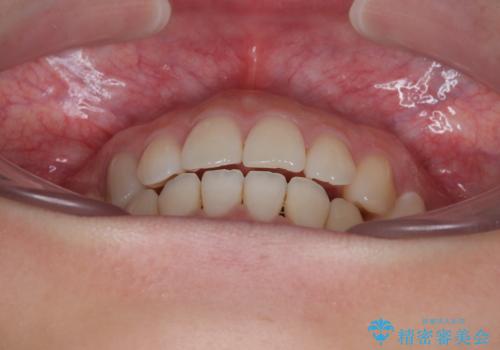

- 口元の突出感と上下前歯のズレを気にして来院された患者様です。

舌の突出癖により上下の前歯は非接触となっている状態でした。

突出感改善のため、上下左右の第一小臼歯4本を抜歯し、ワイヤー装置にて矯正治療を行うこととしました。

舌のトレーニングをしっかりと行ってくださり、予定通りの期間で理想的な仕上がりを達成することができました。